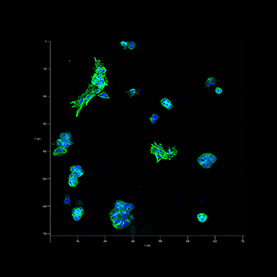

Our bodies have an impressive capacity to heal themselves; unfortunately, the nervous system regenerates much less easily than other vital tissues. Implants of materials that can support or guide the regrowth of cells could help the nervous system recover from injury or disease.

These images reveal the efforts of researchers to coax rat brain cells to grow across a surface of graphene, a material chosen for its toughness, flexibility, and ability to conduct electrical signals. The cells cannot easily implant on the graphene, and in early trials clung to each other instead. In later trials, the addition of the right mix of proteins to the graphene surface enabled cells to implant, grow, and form a healthy, web-like network.